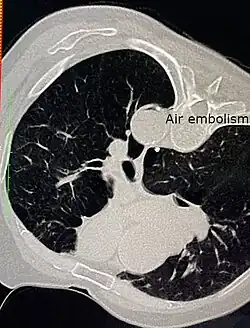

Air embolism